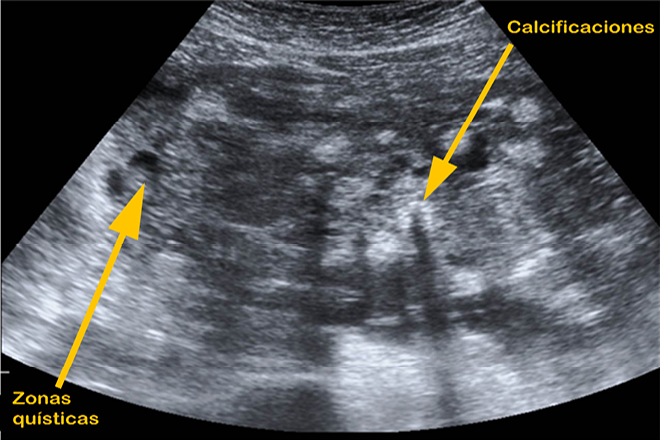

Teratoma quístico

Teratoma quístico Conocido y más frecuentemente encontrado en la literatura como teratoma ovárico o como quiste dermoide, se trata de un tumor con apariencia quística, derivado de inclusiones embriológicas anormales de las diferentes capas del ovario (ecto, meso y endodermo) durante su desarrollo. La característica principal de este tipo de